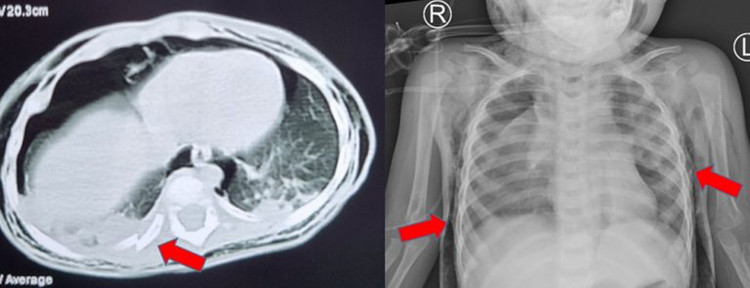

| Sau gần 2 tuần điều trị phẫu thuật khâu vỡ khí quản, tình trạng trẻ cải thiện, phục hồi, tỉnh táo, cai máy thở khí trời - Ảnh BVCC |

Kết quả sau gần 2 tuần điều trị, tình trạng trẻ cải thiện, dần hết tràn khí trung thất, dưới da, được cai máy thở, rút ống dẫn lưu màng phổi. Trẻ tỉnh táo thở khí trời. Đây là tình trạng chấn thương vỡ khí quản hiếm gặp ở trẻ em.